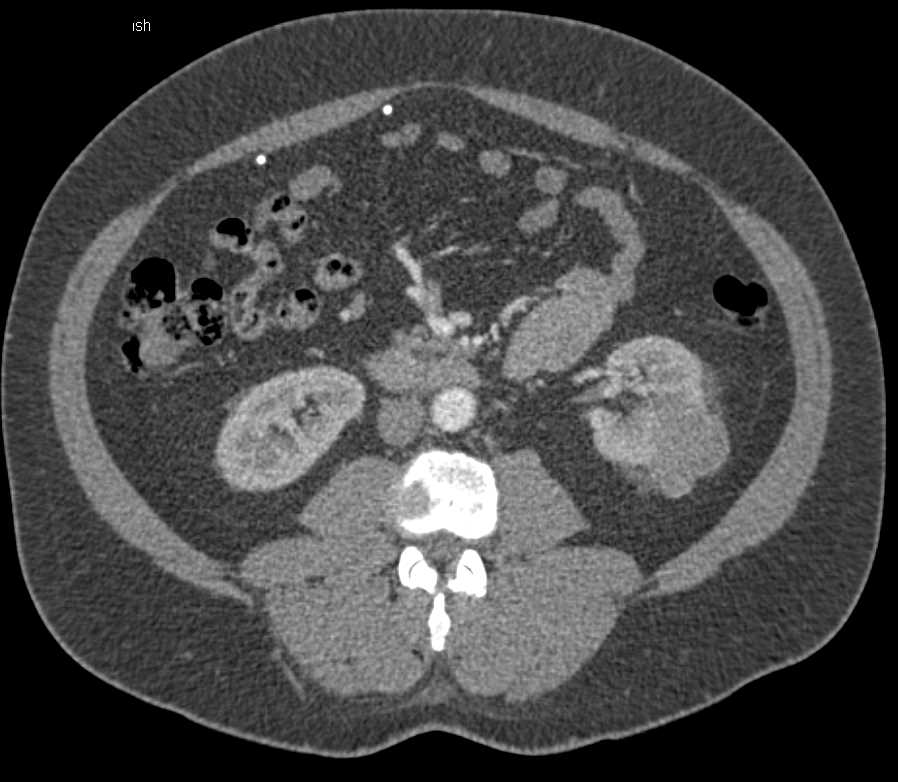

Bosniak 2F Cyst Left Kidney